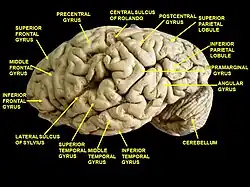

Left cerebral hemisphere seen from above. Lateral surface of left cerebral hemisphere.

Lateral surface of right cerebral hemisphere. Middle frontal gyrus is noted by red arrows. Cerebrum. Lateral view.Deep dissection.

Cerebrum. Lateral view.Deep dissection. Cerebrum. Lateral view.Deep dissection.